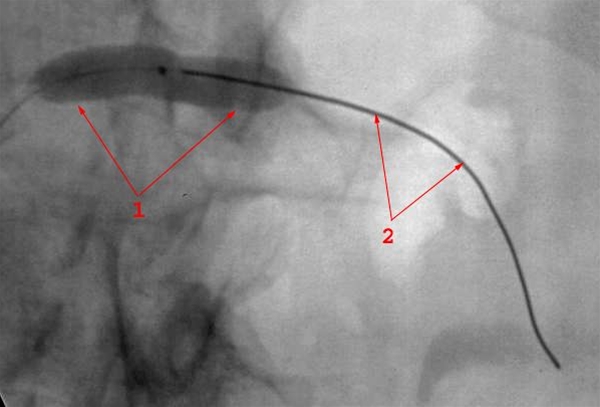

Forsnævring (stenose) (1) i venstre nyrearterie lige efter afgangen fra legemspulsåren (aorta) er behandlet med ballonudvidelse. Ballonen er indført via pulsåren i lysken, ført baglæns op i aorta og så ud i nyrearterien ledt af en guide-wire (2), som er lagt gennem stenosen.